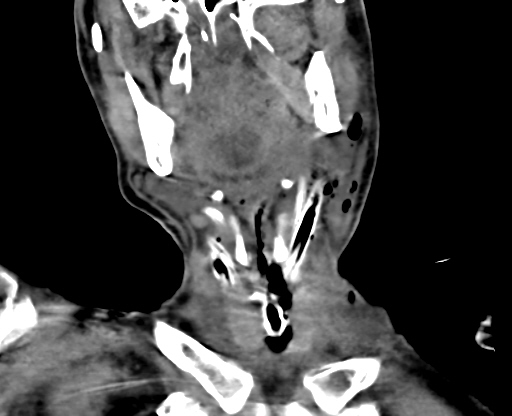

图片

▲治疗第5天颈部(冠状位),胸部(轴位)